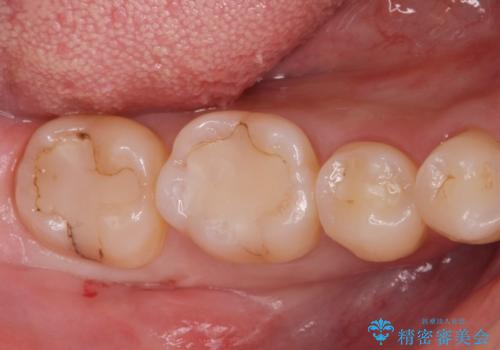

[ 歯並びと虫歯治療 ] 矯正治療とセラミック治療の包括治療

![[ 歯並びと虫歯治療 ] 矯正治療とセラミック治療の包括治療の症例 治療前](https://seimitsushinbi.jp/wp/wp-content/uploads/2023/12/IMG_1093-500x350.jpg?v=1703058764)